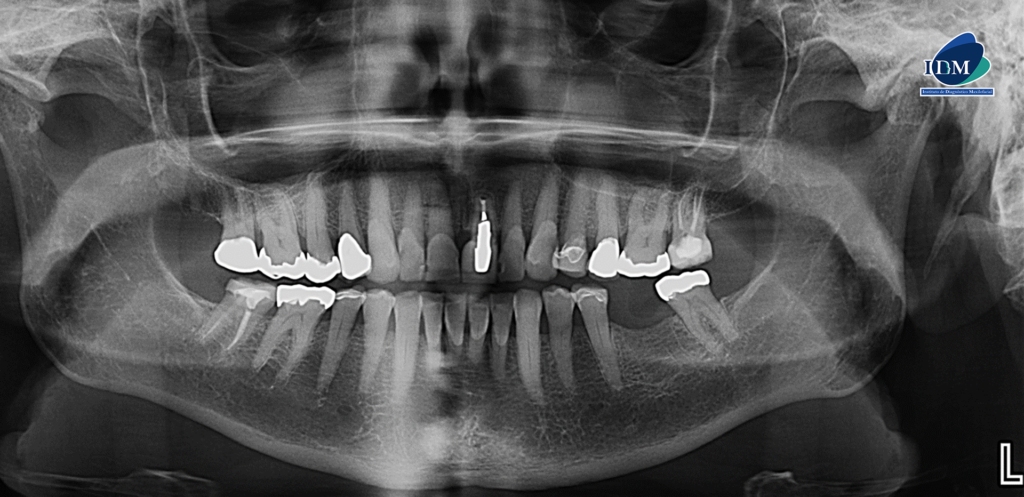

Radiografia Panorámica

A la evaluación de la radiografía panorámica se evidencia un aplanamiento severo del contorno de cóndilos mandibulares.